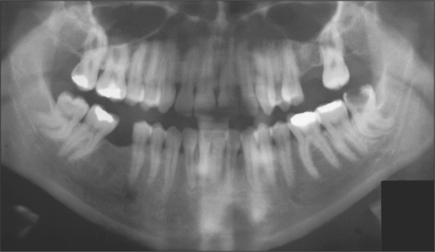

The radiographic examination of choice is a panoramic radiograph such as an OPT (Fig. 5.3), although periapical or oblique lateral views of the mandible may be taken as an alternative. When referring a case for treatment all recent relevant radiographs should be included to avoid further exposure to ionizing radiation.

image

Fig. 5.3 A mesioangular impacted lower third molar on the right and distoangular impaction on the left. (Note the unerupted third molars in the maxilla.)